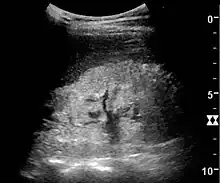

One of the primary indications for referral to US evaluation of the kidneys is evaluation of the urinary collecting system. Enlargement of the urinary collecting system is usually related to urinary obstruction and can include the pelvis, the calyces and the ureter. Hydronephrosis is seen as an anechoic fluid-filled interconnected space with enhancement within the renal sinus, and normally, the dilated pelvis can be differentiated from the dilated calyces.[1]

Figure 13. Hydronephrosis due to ureteropelvic junction obstruction in a pediatric patient.[1]

Several conditions can result in urinary obstruction. In both adults and children, masses, such as abscesses and tumors, can compress the ureter. In children, hydronephrosis can be caused by ureteropelvic junction obstruction, ectopic inserted ureter, primary megaureter and posterior urethral valve (Figure 13). In the latter, both kidneys will be affected. In adults, hydronephrosis can be caused by urolithiasis, obstructing the outlet of the renal pelvis or the ureter, and compression of the ureter from, e.g., pregnancy and retroperitoneal fibrosis. Urolithiasis is the most common cause of hydronephrosis in the adult patient and has a prevalence of 10%–15%.[1]